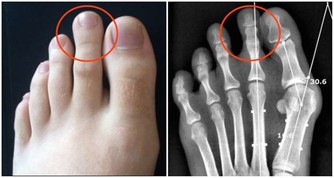

雖然X光片在臨床應用廣泛,但因分辨率較低,對於微小以及隱蔽部位的病灶,都不易發現到。用其篩查肺癌漏診率相當高,到用X光能夠查出時,多數已是中晚期了。

而實際上,目前醫學界公認篩查早期肺癌最有效的手段是——低劑量螺旋CT,其發現早期肺癌的敏感度是常規胸片的4~10倍,大大提高肺癌的治愈率和存活率。